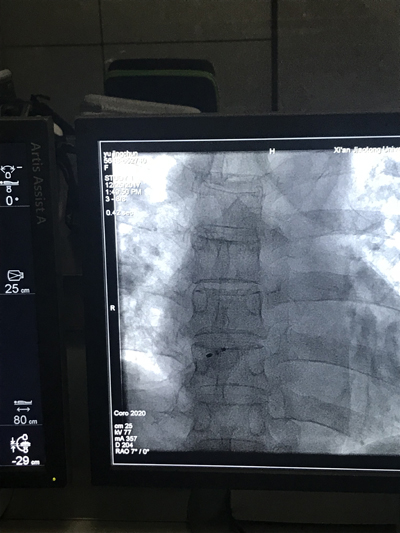

12月25日,心血管病院成功开展卵圆孔未闭介入封堵术,该手术为本院首例。患者为一名56岁的女性,1月前因头晕住院,伴言语不清、行走不稳,行头颅MRI示左侧丘脑新鲜腔梗。TCD发泡试验阳性。行心脏彩超示卵圆孔未闭。经手术团队评估后,决定为其进行卵圆孔未闭封堵术。手术由董新主任医师、张玉顺主任医师、李青医师共同操作,在导丝引导下,通过封堵器输送系统将封堵器通过房间隔左房面,打开封堵器,在超声及X光透视下判定其位置准确、稳固后,释放封堵器,手术成功。手术过程仅用时30分钟。其后,又顺利完成两例先天性心脏病(房间隔缺损、动脉导管未闭)患者的封堵术。